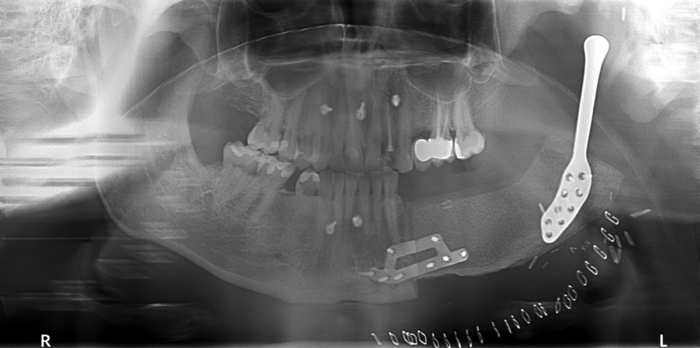

One of the most complex surgeries performed in the clinic involved the reconstruction of the temporomandibular joint using a 3D-printed alloplastic material. This procedure also included the application of a custom-designed iliac crest osteomyocutaneous flap, harvested with the aid of an individualized template. This innovative approach significantly enhances treatment options for patients with craniofacial cancers, substantially improving their quality of life.